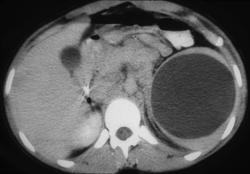

Subcapsular Splenic Hematoma